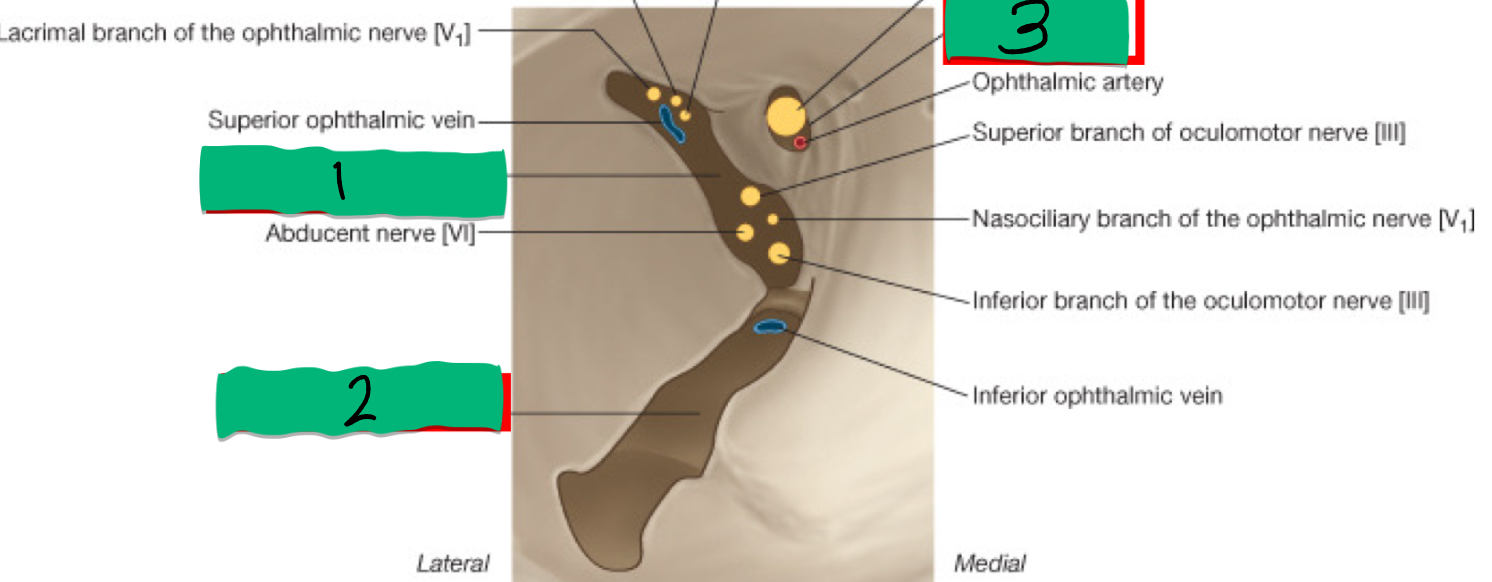

1

Optic Canal: CN II

2

Superior Orbital Fissure: CN III, IV, V1, VI

3

Foramen Rotundum: V2